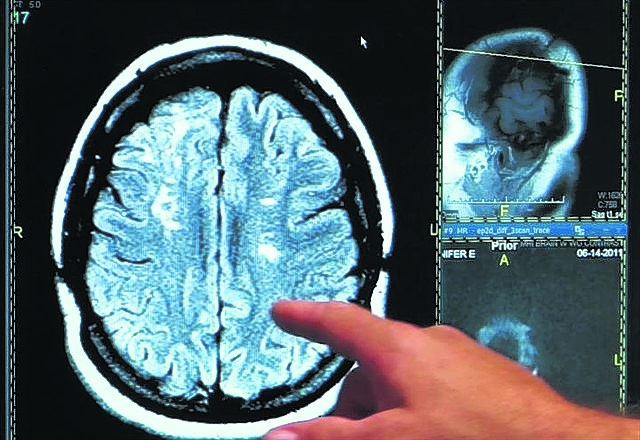

Hace décadas, se daba por sentado que el mayor período de desarrollo cerebral sucedería en los primeros años de vida, pero en ese entonces no contábamos con las herramientas necesarias para mirar dentro del cerebro y determinar con mayor precisión su desarrollo en las diferentes etapas de la vida. Los grandes avances en métodos tales como la RMN estructural y funcional nos permiten entender que no todo termina de desarrollarse en los primeros años de vida, sino que el desarrollo cerebral continúa hasta pasados los 20 años. La adolescencia se trata de una de las etapas de transición más importantes en la vida del ser humano y se caracteriza por un ritmo acelerado de crecimiento y cambios.

Desarrollos desparejos y disparatados subyacen a esas conductas. La región prefrontal del cerebro, que se ocupa de las llamadas funciones ejecutivas y del control de impulsos, se va desarrollando lentamente y a un ritmo parejo a través de la adolescencia. A medida que los niños crecen y se convierten en adolescentes y luego en adultos, el desempeño en tareas de control de impulsos va mejorando, logrando gradualmente resistirse a las recompensas inmediatas, considerando el largo plazo, a través de esta maduración lineal de esta región cerebral.

Por el contrario, otras regiones (subcorticales) relacionadas con la emoción, la motivación y la recompensa, presentan un desarrollo rápido en la adolescencia temprana, sobrepasando la lenta maduración de las regiones prefrontales. Dado que las interacciones entre la corteza prefronal y estas regiones subcorticales juegan un rol fundamental en la regulación de la conducta, la disparidad entre los componentes emocionales e intelectuales en la toma de decisiones adolescente genera decisiones sesgadas y vulnerables.